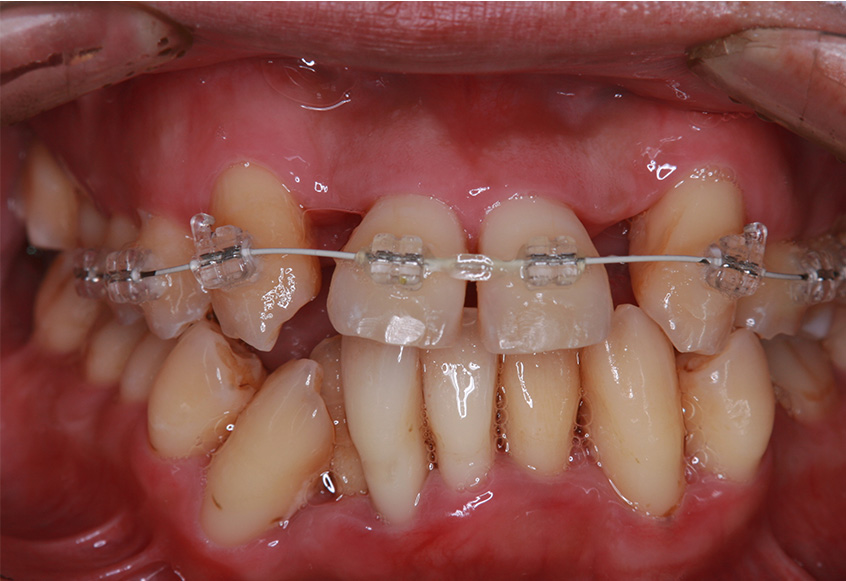

最初のお口の中 治療開始3ヵ月後

-

6ヵ月経過すると、矯正治療を終了し、前歯に被せ物の治療を行いました。

最初のお口の中 2025/3/22

被せ物装着